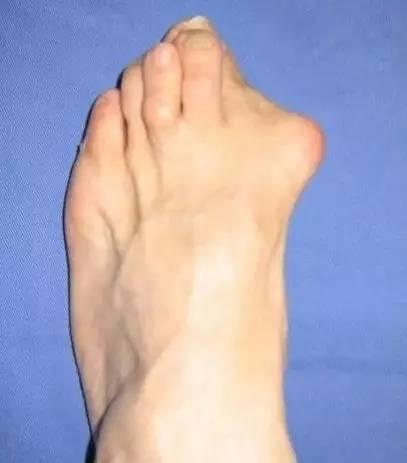

其实她们都得了一种叫拇外翻的病。

拇外翻,俗称大脚骨病,表现为大脚趾根部骨骼明显外凸,大脚趾尖向第二脚趾靠拢。随着年龄的增加,拇外翻畸形程度会加重,能产生很多并发症,如拇囊炎肿、爪形趾、鸡眼、疼痛型脚垫等。